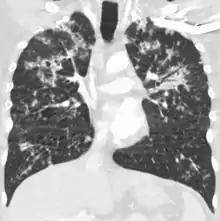

A case of miliary tuberculosis in an 82-year-old woman:

X-ray, 13 days after onset, showing bilateral interstitial infiltrates

CT, 16 days after onset, showing extensive pulmonary parenchymal involvement consisting of irregular septal thickenings with ground-glass areas and centrilobular nodules with a peri-lymphatic distribution

X-ray, 22 days after onset, showing extensive bilateral reticulo-nodular infiltrates